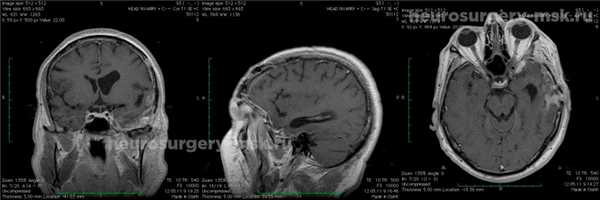

После удаления образования отмечается быстрое восстановление силы мышц в работе правой руки. Полностью прекратились боли головного типа, устранены все нарушения речевого характера. После удаления менингиомы средней черепной ямки производится контроль посредством МРТ.

Менингиома средней черепной ямки (после операции)